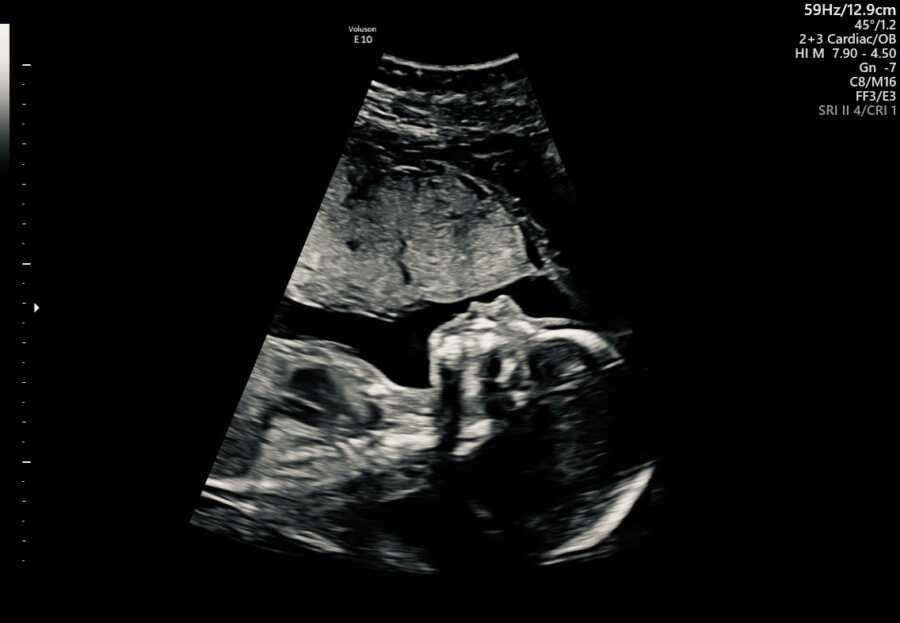

Fetal Cardiac Ultrasound Baby Girl Heartbeat In Utero The average heart rate for baby boys in the first trimester was 154.9 bpm (plus or minus 22.8 bpm) and for. a normal fetal heart rate (fhr) usually ranges from 120 to 160 beats per minute (bpm) in the in utero period. at about five weeks gestation, your baby's heart begins to beat. At this point, a normal. Baby Girl Heartbeat In Utero.